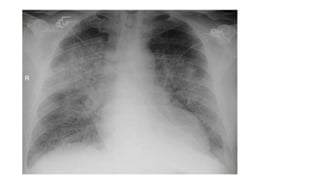

This document provides an overview of heart failure. It begins by outlining the objectives of understanding pathophysiology, classification, therapeutic targets, and initiating guideline directed medical therapy. It then discusses the anatomy, myocardial mechanics, effects on physiology, and introduction to heart failure. Classification systems such as ESC and AHA/ACC are presented. The document discusses heart failure in India, hospitalization risk, definition, and why ejection fraction is used for classification. It covers the pathophysiology, signs and symptoms, assessment, biomarkers, ECG, CXR findings, echocardiogram evaluation, treatment approaches for acute and chronic heart failure, guideline directed medical therapies including drugs, and SGLT2 inhibitors.